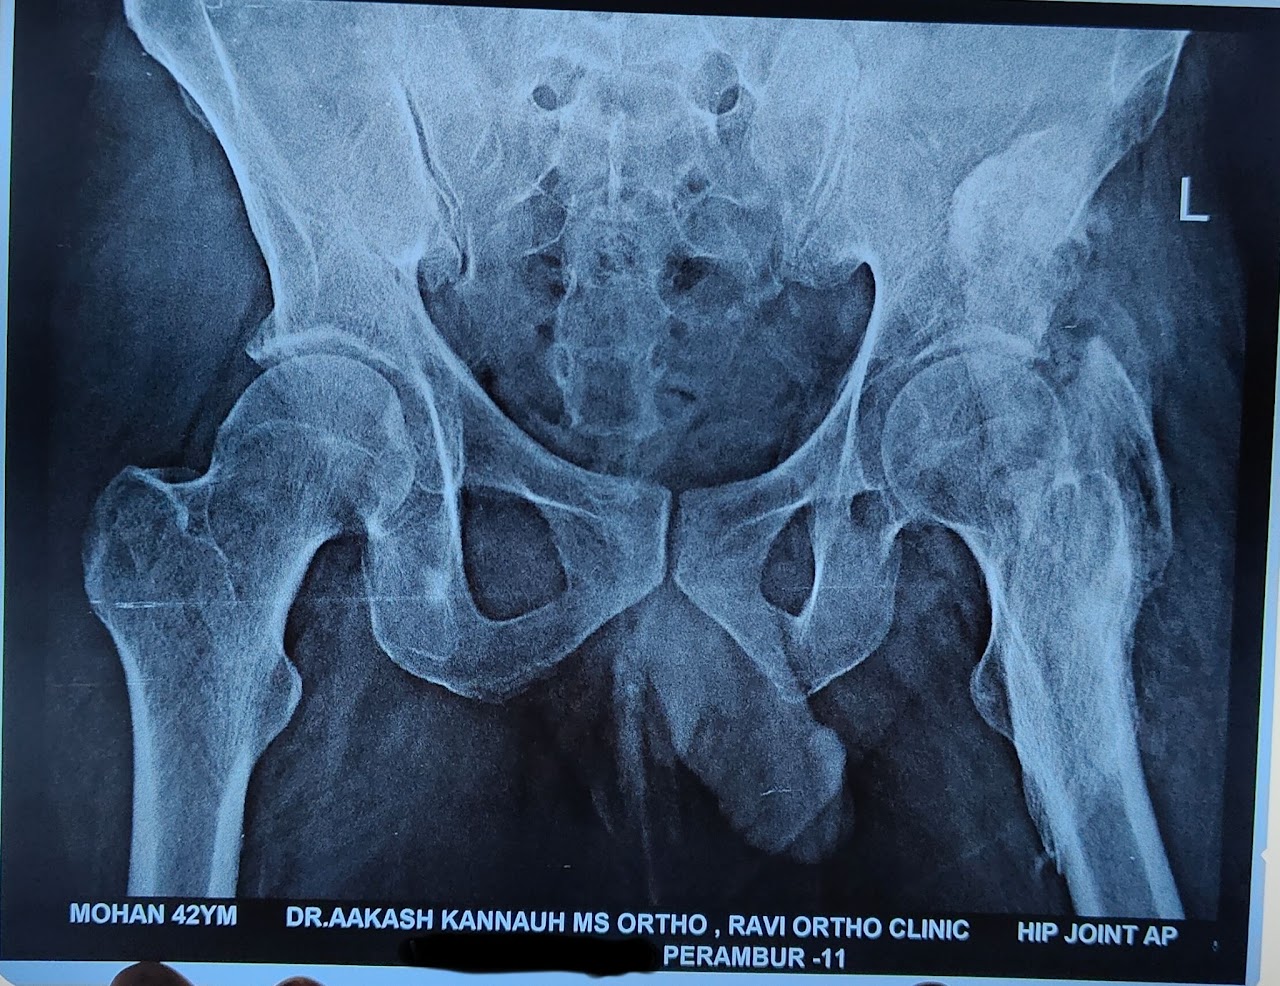

X-ray

- Advanced digital X-ray for accurate diagnosis

- Quick imaging with minimal waiting time

- High-quality and clear imaging results

- Supports effective treatment planning

- Safe and reliable diagnostic process